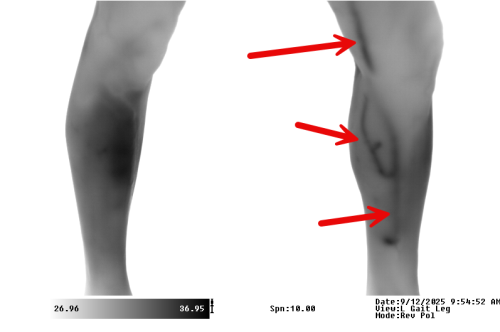

Spectron IR Medical Infrared Images